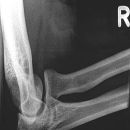

Ellenbogen seitlich

Patient sitzt seitlich am Tisch, Oberarm und Unterarm auf Schulterhöhe waagerecht aufliegend, Gelenk im Winkel von 90° gebeugt, Unterarm liegt ulnar auf, Daumen zeigt nach oben bei streng seitlicher Handstellung, Unterarm evtl. unterpolstern.

Senkrecht auf Gelenk- und Filmmitte.

Weitgehend freie Projektion des Radiusköpfchens, das sich als Oval abzeichnet, lediglich vom Processus coronoideus anteilig überlagert

Ellenbogengelenk vollständig seitlich orthograd abgebildet. Humeroulnar Gelenkspalt einsehbar. Humeruskondylen müssen sich decken, das Radiusköpfchen soll gut beurteilbar sein.